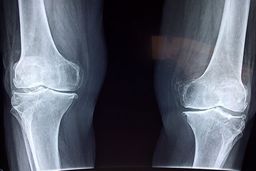

فوق تخصص بیماریهای روماتولوژی با اشاره به اهمیت پیشگیری و تشخیص زودهنگام پوکی استخوان گفت: این بیماری به کاهش مواد…